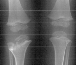

A three year one month old boy presented to AIDI with shortening of the right humerus. Clinical examination revealed 4 cm shortening of right arm and painless limitation of ROM of right shoulder; abduction was 150 degrees with 80 degrees at the glenohumeral joint and internal rotation was significantly limited. There was also 1 cm shortening of the right leg and a 10 degree valgus deformity of the same knee.

Radiological examination showed absence of proximal epiphysis of the right humerus with marked deformity of the metaphyseal region. There was mild shortening of the right tibia in association with destruction of the lateral part of the proximal metaphysis and epiphysis. The diagnosis was neonatal sepsis with multifocal osteomyelitis involving the right humerus and proximal right tibia.